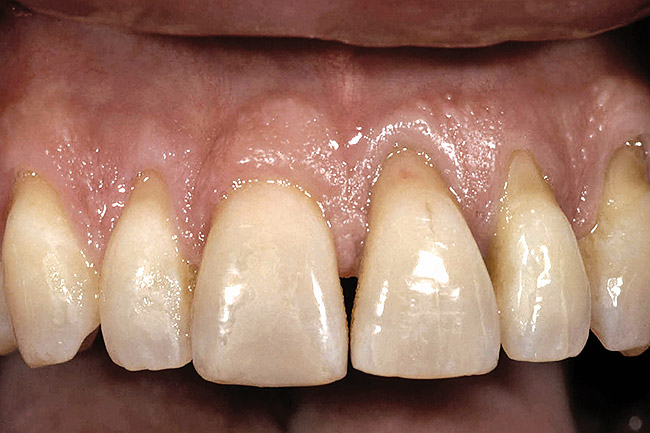

Figure 5  A patient presented needing both centrals extracted. Note the excellent papillary height and free gingival margin location.

Figure 5